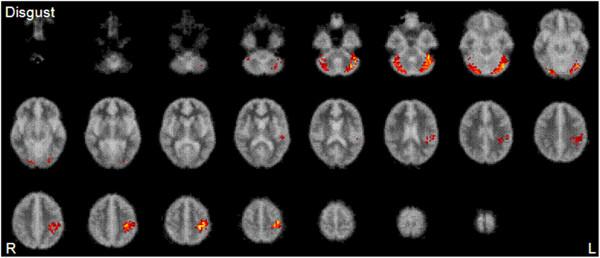

We used event-related functional magnetic resonance imaging (fMRI) to examine neural responses when children with 22q11DS (aged 9-17 years) and healthy controls (aged 8-17 years) incidentally processed neutral expressions and mild (50%) and intense (100%) expressions of fear and disgust. We included 28 right-handed children and adolescents: 14 with 22q11DS and 14 healthy (including nine siblings) controls.

Within groups, contrasts showed that individuals significantly activated 'face responsive' areas when viewing neutral faces, including fusiform-extrastriate cortices. Further, within both groups, there was a significant positive linear trend in activation of fusiform-extrastriate cortices and cerebellum to increasing intensities of fear. There were, however, also between-group differences. Children with 22q11DS generally showed reduced activity as compared to controls in brain regions involved in social cognition and emotion processing across emotion types and intensities, including fusiform-extrastriate cortices, anterior cingulate cortex (Brodmann area (BA) 24/32), and superomedial prefrontal cortices (BA 6). Also, an exploratory correlation analysis showed that within 22q11DS children reduced activation was associated with behavioural impairment-social difficulties (measured using the Total Difficulties Score from the Strengths and Difficulties Questionnaire [SDQ]) were significantly negatively correlated with brain activity during fear and disgust processing (respectively) in the left precentral gyrus (BA 4) and in the left fusiform gyrus (FG, BA 19), right lingual gyrus (BA 18), and bilateral cerebellum.

Regions involved in face processing, including fusiform-extrastriate cortices, anterior cingulate gyri, and superomedial prefrontal cortices (BA 6), are activated by facial expressions of fearful, disgusted, and neutral expressions in children with 22q11DS but generally to a lesser degree than in controls. Hypoactivation in these regions may partly explain the social impairments of children with 22q11DS.